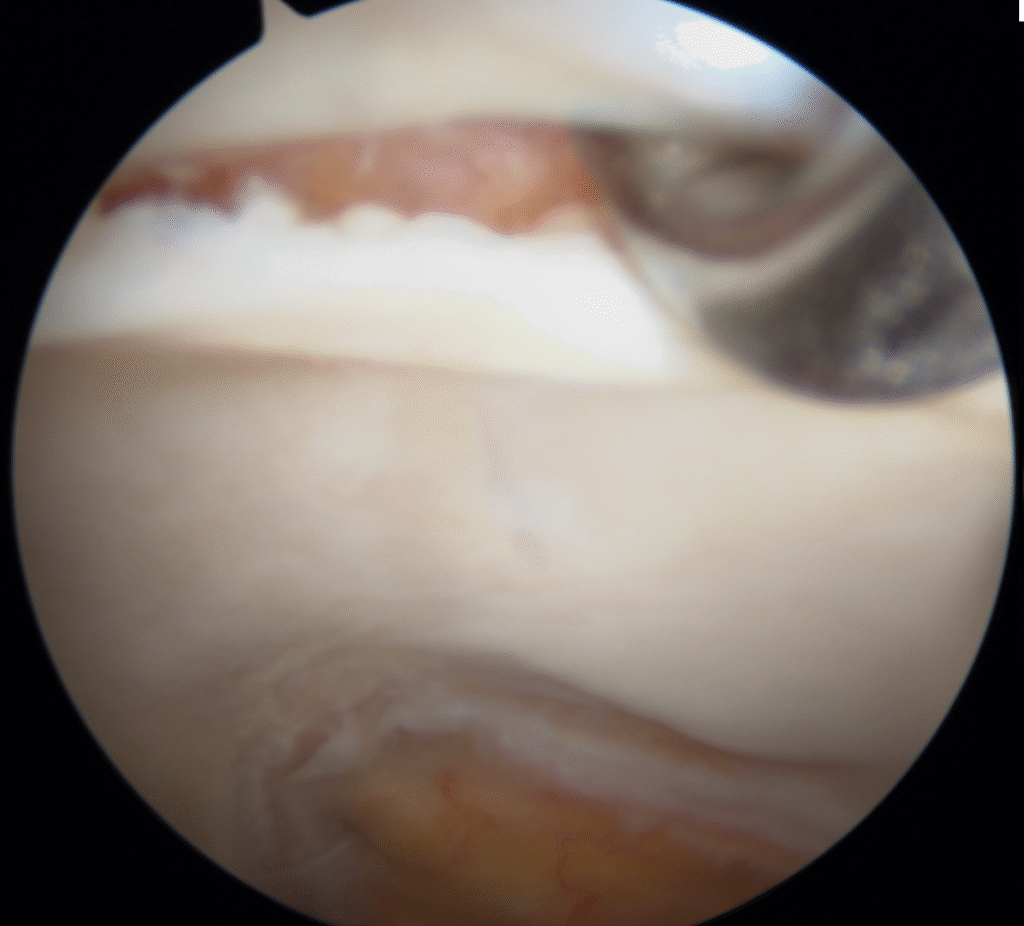

Na artroscopia é possível reparar ou limpar as lesões do labrum e algumas lesões da cartilagem articular, remover corpos livres intra articulares e regularizar algumas alterações ósseas presentes no conflito femuro-acetabular.

Atualmente a indicação mais frequente para a artroscopia da anca é o conflito femuro-acetabular. É uma técnica pouco invasiva e segura mas apresenta uma curva de aprendizagem considerável